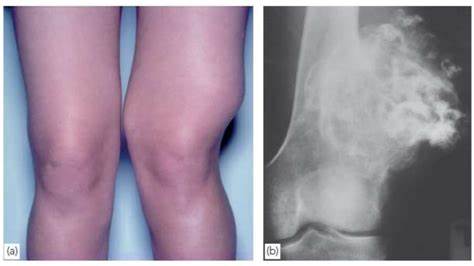

이유없는 통증이 시작되고 밤에 주로 심해진다거나, 사지나 척추 등에 종괴가 만저지거나 영상검사에서 확인되면 '근골격계 종양' 을 항상 감별을 하도록 해야합니다. 종양의 경우 '나이' 가 가�